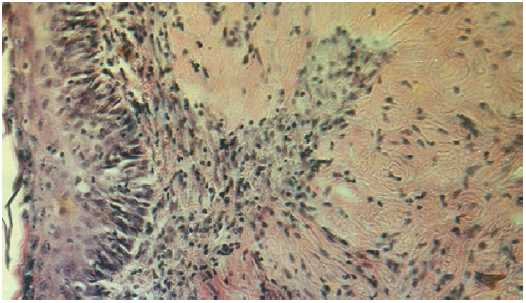

В гистологических препаратах контрольной группы животных эпидермис кожи имеет неровные контуры разной толщины, с выраженной отслойкой рогового слоя эпидермиса. Ростковая зона эпидермиса образует сложные складки (рис. 1), растущие навстречу с двух краев раны. Складчатость эпидермиса кожи обусловлена образованием плотной неоформленной соединительной ткани.

Рис. 1. Неравномерное разрастание эпидермиса кожи белых крыс при травме. Окраска гематоксилин-эозином. Микрофото. Ок. 10, об. 20